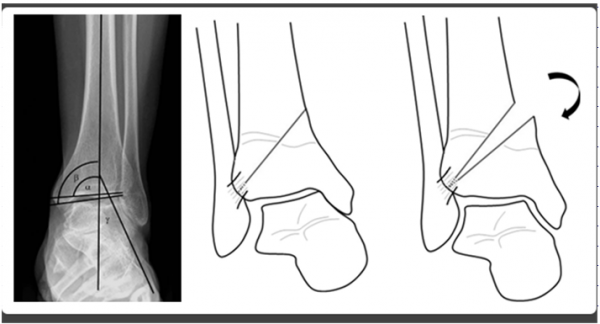

무릎에도 관절염이 있듯이 발목에도 관절염이 있습니다. 하지만 무릎이 퇴행성 관절염인 것과는 달리, 발목은 외상성 관절염이 많다는 차이가있습니다. 물론 발목에도 퇴행성 관절염이나 류머티스 관절염이 흔하게 발생합니다. 그러나, 발목 염좌나 발목 부위 골절의 후유증으로연골손상이 진행되는 경우에는 외상성 관절염이 발생합니다.